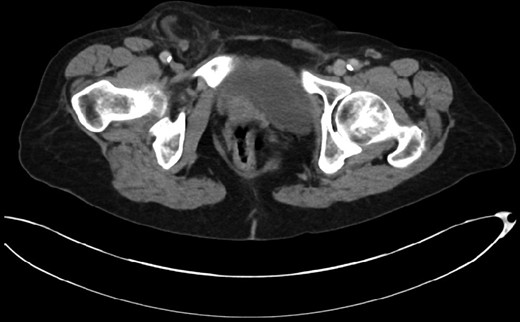

This 82-year-old lady presented with a sudden painful right sided groin swelling not previously noticed. She had no features of obstruction and was opening her bowels and not vomiting. Her medical background included left sided femoral hernia repair in 2005, coronary artery bypass graft and bilateral total knee replacements. On examination her abdomen was soft with the presence of a tender, irreducible swelling in the right groin, inferolateral to the pubic tubercle. She had good bowel sounds and there was stool present in the rectum on PR examination. A full set of blood tests demonstrated no abnormality. A CT abdomen and pelvis demonstrated an incarcerated right sided femoral hernia containing an 8 mm long inflamed appendix with a small amount of localized free fluid and inflammation indicative of De Garengeot’s hernia with underlying acute appendicitis (Fig. 1). The hernia sac diameter measured 2 mm on CT scan. She was taken to theatre for an open Lockwood repair of her femoral hernia and an appendicectomy. Following an initial Lockwood incision over the lump, dissection was performed down to the hernia sac also exposing the inguinal ligament (Fig. 2). The tightness of the femoral ring made mobilization of the appendix difficult. By partially incising the inguinal ligament superior to the femoral ring, the appendix was freed, and on inspection showed inflammation particularly towards the tip (Fig. 3). The caecum was then reduced and the inguinal ligament was repaired with non-absorbable suture. The femoral hernia was then repaired with a small funnel of ultrapro mesh. Appendicectomy was then performed in the usual fashion via the Lockwood incision leaving a slightly longer stump than usual (Fig. 4).

CT scan of the abdomen and pelvis demonstrating acute appendicitis within a femoral hernia.